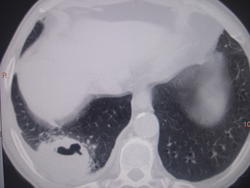

Больной лечился у невролога, провели проф ФГ- выявили деструктивную пневмонию, пролечилили, на Р контроле- ухудшение, клиники абсцесса не было, была боль в гр клетке спереди справа. Из анамнеза- лечился оперативно 6-7 лет назад по поводу рака верхней губы, в ООД не наблюдался последние годы. Данные за туб этиологию сомнительны, как мне кажется, очагов отсева по слоям не вижу,  хотя мож не так смотрю. Ваше мнение коллеги, абсцесс это или нет?

Вполне может быть и полостной формой рака с периканкрозной пневмонией. Пока исследуют мокроту на БК, АК и микрофлору с чувствительностью к антибиотикам, пока лечат, придёт время и для КТ-контроля после лечения. В зависимости от рукастости хирургов, можно было б и пропунктировать - но тут в каждом монастыре свой устав)).

По опыту хочу сказать, что в настоящее время классической клиники абсцесса можете и не увидеть. Очень она изменилась. В данном случае контроль  должен помочь. В связи с тем, что стенки имеют разную толщину и вокруг почти нет изменений, больше склоняюсь к полостной форме рака.